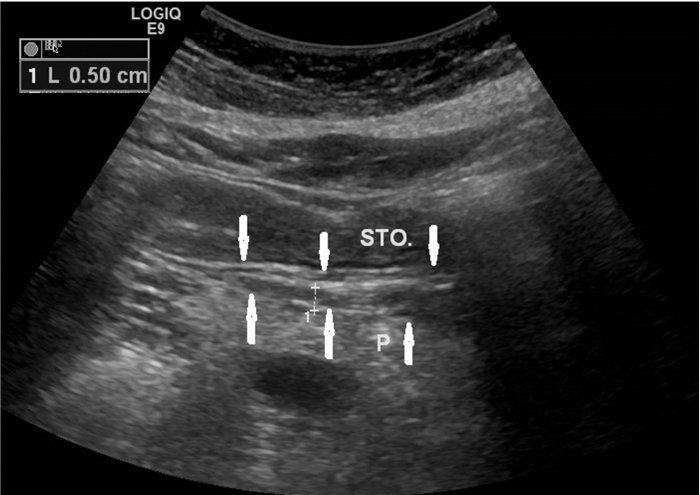

31例MSAP及SAP患者超声显示胰腺均肿大,边缘不规则,边界不清,胰腺实质回声分布不均匀,可见粗大强回声斑或低回声及无回声混杂,其中6例超声提示胰腺脓肿或胰周假性囊肿形成,呈类圆形低回声或无回声区,边界欠清(图 3);29例小网膜囊增厚,呈片状或块状增强回声带,部分内合并有无回声区(图 4)。

| 小网膜囊增厚,最厚约2.0 cm,呈片状增强回声带,内合并有液性无回声区,胰腺边缘不规则,与小网膜囊分界不清,胰腺内部回声不均匀;STO:胃;P:胰腺 图 4 重症急性胰腺炎(SAP)超声所见 |